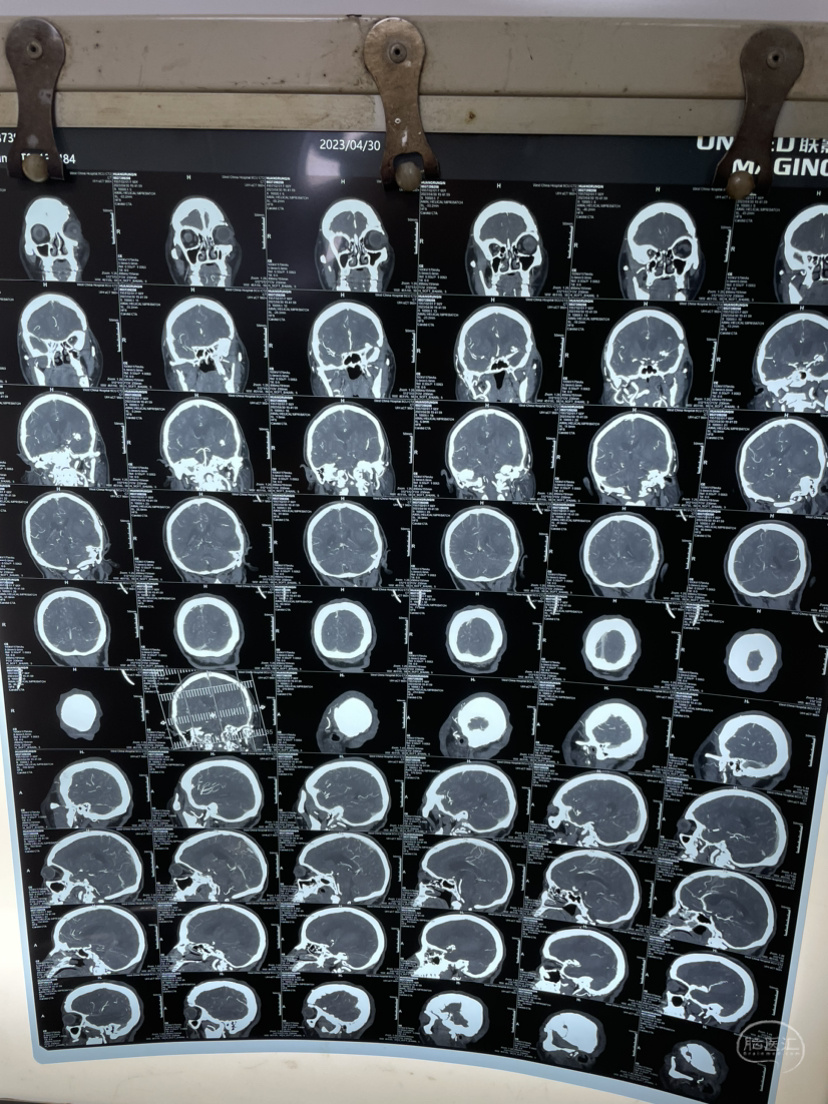

夹闭术后两个月,出院后一个月!再次出血,血肿量大,患者清醒!转上级市级医院,拟予介入栓塞后清除血肿

家属选择保守治疗,患者一直清醒!两个月前在华西行介入栓塞术,血肿吸收!

介入栓塞术后两个月来复查!患者清醒轮椅而来,言语稍含糊,右侧下肢肌力可大于三级,上肢一级!